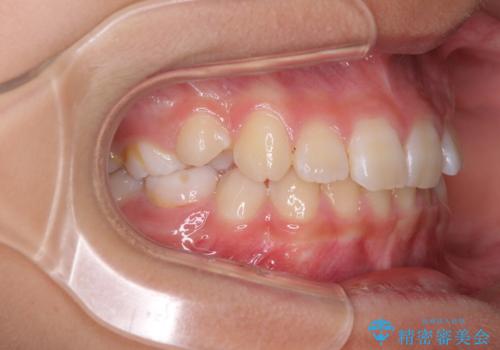

埋もれた犬歯を引っ張り出す 小学生のⅠ期治療

- 小学校での定期歯科検診にて歯列不正を指摘されたとのことで来院された患者様です。

左上の犬歯が低位に埋伏しており、将来八重歯になるリスクが高いと判断されたため、補助装置とワイヤーを用いて犬歯を通常の位置まで移動させることとしました。